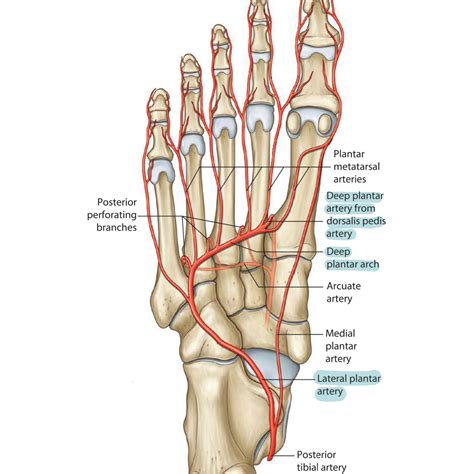

The dorsalis pedis artery is the primary blood vessel supplying the dorsum (top) of the foot. It is a direct continuation of the anterior tibial artery, which descends down the lower leg. Once the anterior tibial artery crosses the ankle joint, it becomes the dorsalis pedis artery. From there, it traverses the foot toward the space between the first and second metatarsals, eventually diving deep to contribute to the plantar arch.

Because the artery runs relatively superficially along the top of the foot, it is often accessible for palpation. However, its exact anatomical path can vary slightly between individuals. In some patients, the vessel may have a more lateral or medial deviation, making it challenging to locate without proper technique. Recognizing these anatomical variations is crucial for clinicians to avoid misinterpreting a "missing" pulse as a sign of vascular disease when it might simply be an anatomical anomaly.